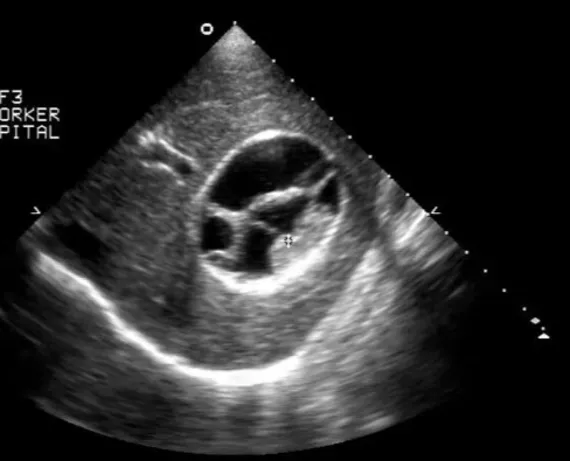

多囊肝

● 肝内无数个无回声区。

● 大者边界清,形态一般欠规整。

● 内透声好。

● 后方结构(后壁)回声增强。

● 无囊肿部位肝组织回声增强增粗。